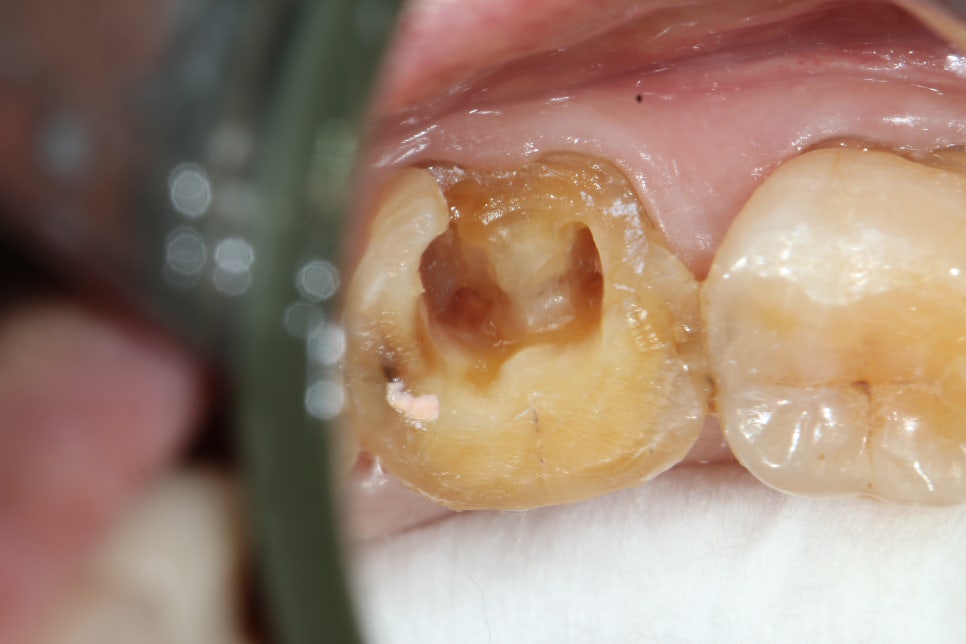

CT 영상(초진)과 standard x-ray 사진(팔라탈 루트 발치 후)

이번 주에 있었던 임상 케이스는 발치 후 생긴 상악동 누공이다. 이미 치관은 썩어 날아갔고 엔도도 되어있었다. 드러난 치근 중간에 GP로 추정되는 연핑크 실오라기가 몇가닥 꼽혀있는 루트레스트 발치케이스. 파노라마상에서 치근이 상악동 내부로 돌출되어 보이기도 하고 반대편엔 cystic lesion도 있어서 술전에 대표원장님께서 미리 CT도 찍어보았는데, 역시나 상악동 내부로 루트가 솟아올라와 있었다. 발치 중에 상악동으로 치근이 전위될 수 있음을 고지하고, 상악동에 구멍이 날 수 있다는 이야기도 반복적으로 설명한 뒤에 동의를 받고 발치를 시작했다.

일단 MB-DB-P 세갈래로 섹셔닝을 하고 가운데에 다이렉타 듀얼엣지 5번 꼽고 돌리는데 엥? 힘을 전혀 못받는다. EL3C로 바꿔서 엘리베이터 꼽고 pdl space에 넣고 돌리니까 마치 요거트 퍼먹듯이 치아가 푹푹 퍼지기만... 치아가 힘을 못 받으니 럭세이션은 커녕 계속 치아는 밑으로 사라져가고, 어쩌다 딱 꼽혀서 럭세이션 좀 되나? 싶으면 윗 부분만 쪼개져서 떨어져나오는 치아. 어떻게 그렇게 반죽이 되는걸까? 엘리베이터 꼽아야하는 위치가 점점 아래로 내려갈 때마다 마음은 불안해진다😢 교도소 공보의할 때도 이런 적이 꽤 있었지. 그래서 조심조심 하기는 해도 멘붕이 오지는 않았다.

여기저기 찔러보다 어찌저찌 구개치근을 꺼냈는데 상악동 막이 눈에 훤히 보인다. 그리고 혈액에 살짝 가려진 구멍도. '작으니까 그냥 둬도 괜찮겠지 교과서에서 그랬잖아~' 생각하면서 그거 보고 있는데 쪽! 하고 석션팁이 와서 혈액을 석션해가니 보이는 거대한 구멍..🤦♂️ 이제 안괜찮아졌다.

중간에 엑스레이 찍어서 남은 치근 위치 확인하고 EL3C로 다 꺼냈는데 상악동 누공이 너무 커보인다. 아마 심리적인 요인으로 더 커보였을 것이다. 돌이켜보면 그렇게까지 크지는 않았을지도? 치과엔 콜라겐 플러그나 큐탄플러스트, 써지셀 그런 건 없는 것 같다 못봤어. 그래서 생각나는 건 플랩 열어 1차봉합 해주는 방법. 얼른 블레이드 달라고 해서 플랩 열고(근데 여태 플랩 안 열고 뭐했니?) 페리오스틸엘리베이터로 박리 넓게 해준 다음 골막 살살 감장절개 해서 땡겨 구개측에 1차봉합 해줬다. 깔끔하지 못해서 영 마음이 안 좋고 해놓고도 마음이 콩닥콩닥 해서 DSLR 사진 찍어 놓고 대표원장님께 보고드렸다. 대표원장님께서 협측에 감장절개 해도 구개측까지 안 당겨져서 1차봉합이 잘 안될 땐 구개측에 horizontal하게 인시전 넣어 플랩 땡겨와 수쳐할 수 있다는 팁도 알려주셨다.(구개측 치은에 일시적으로 defect 생긴 거는 금방 치유된다고)